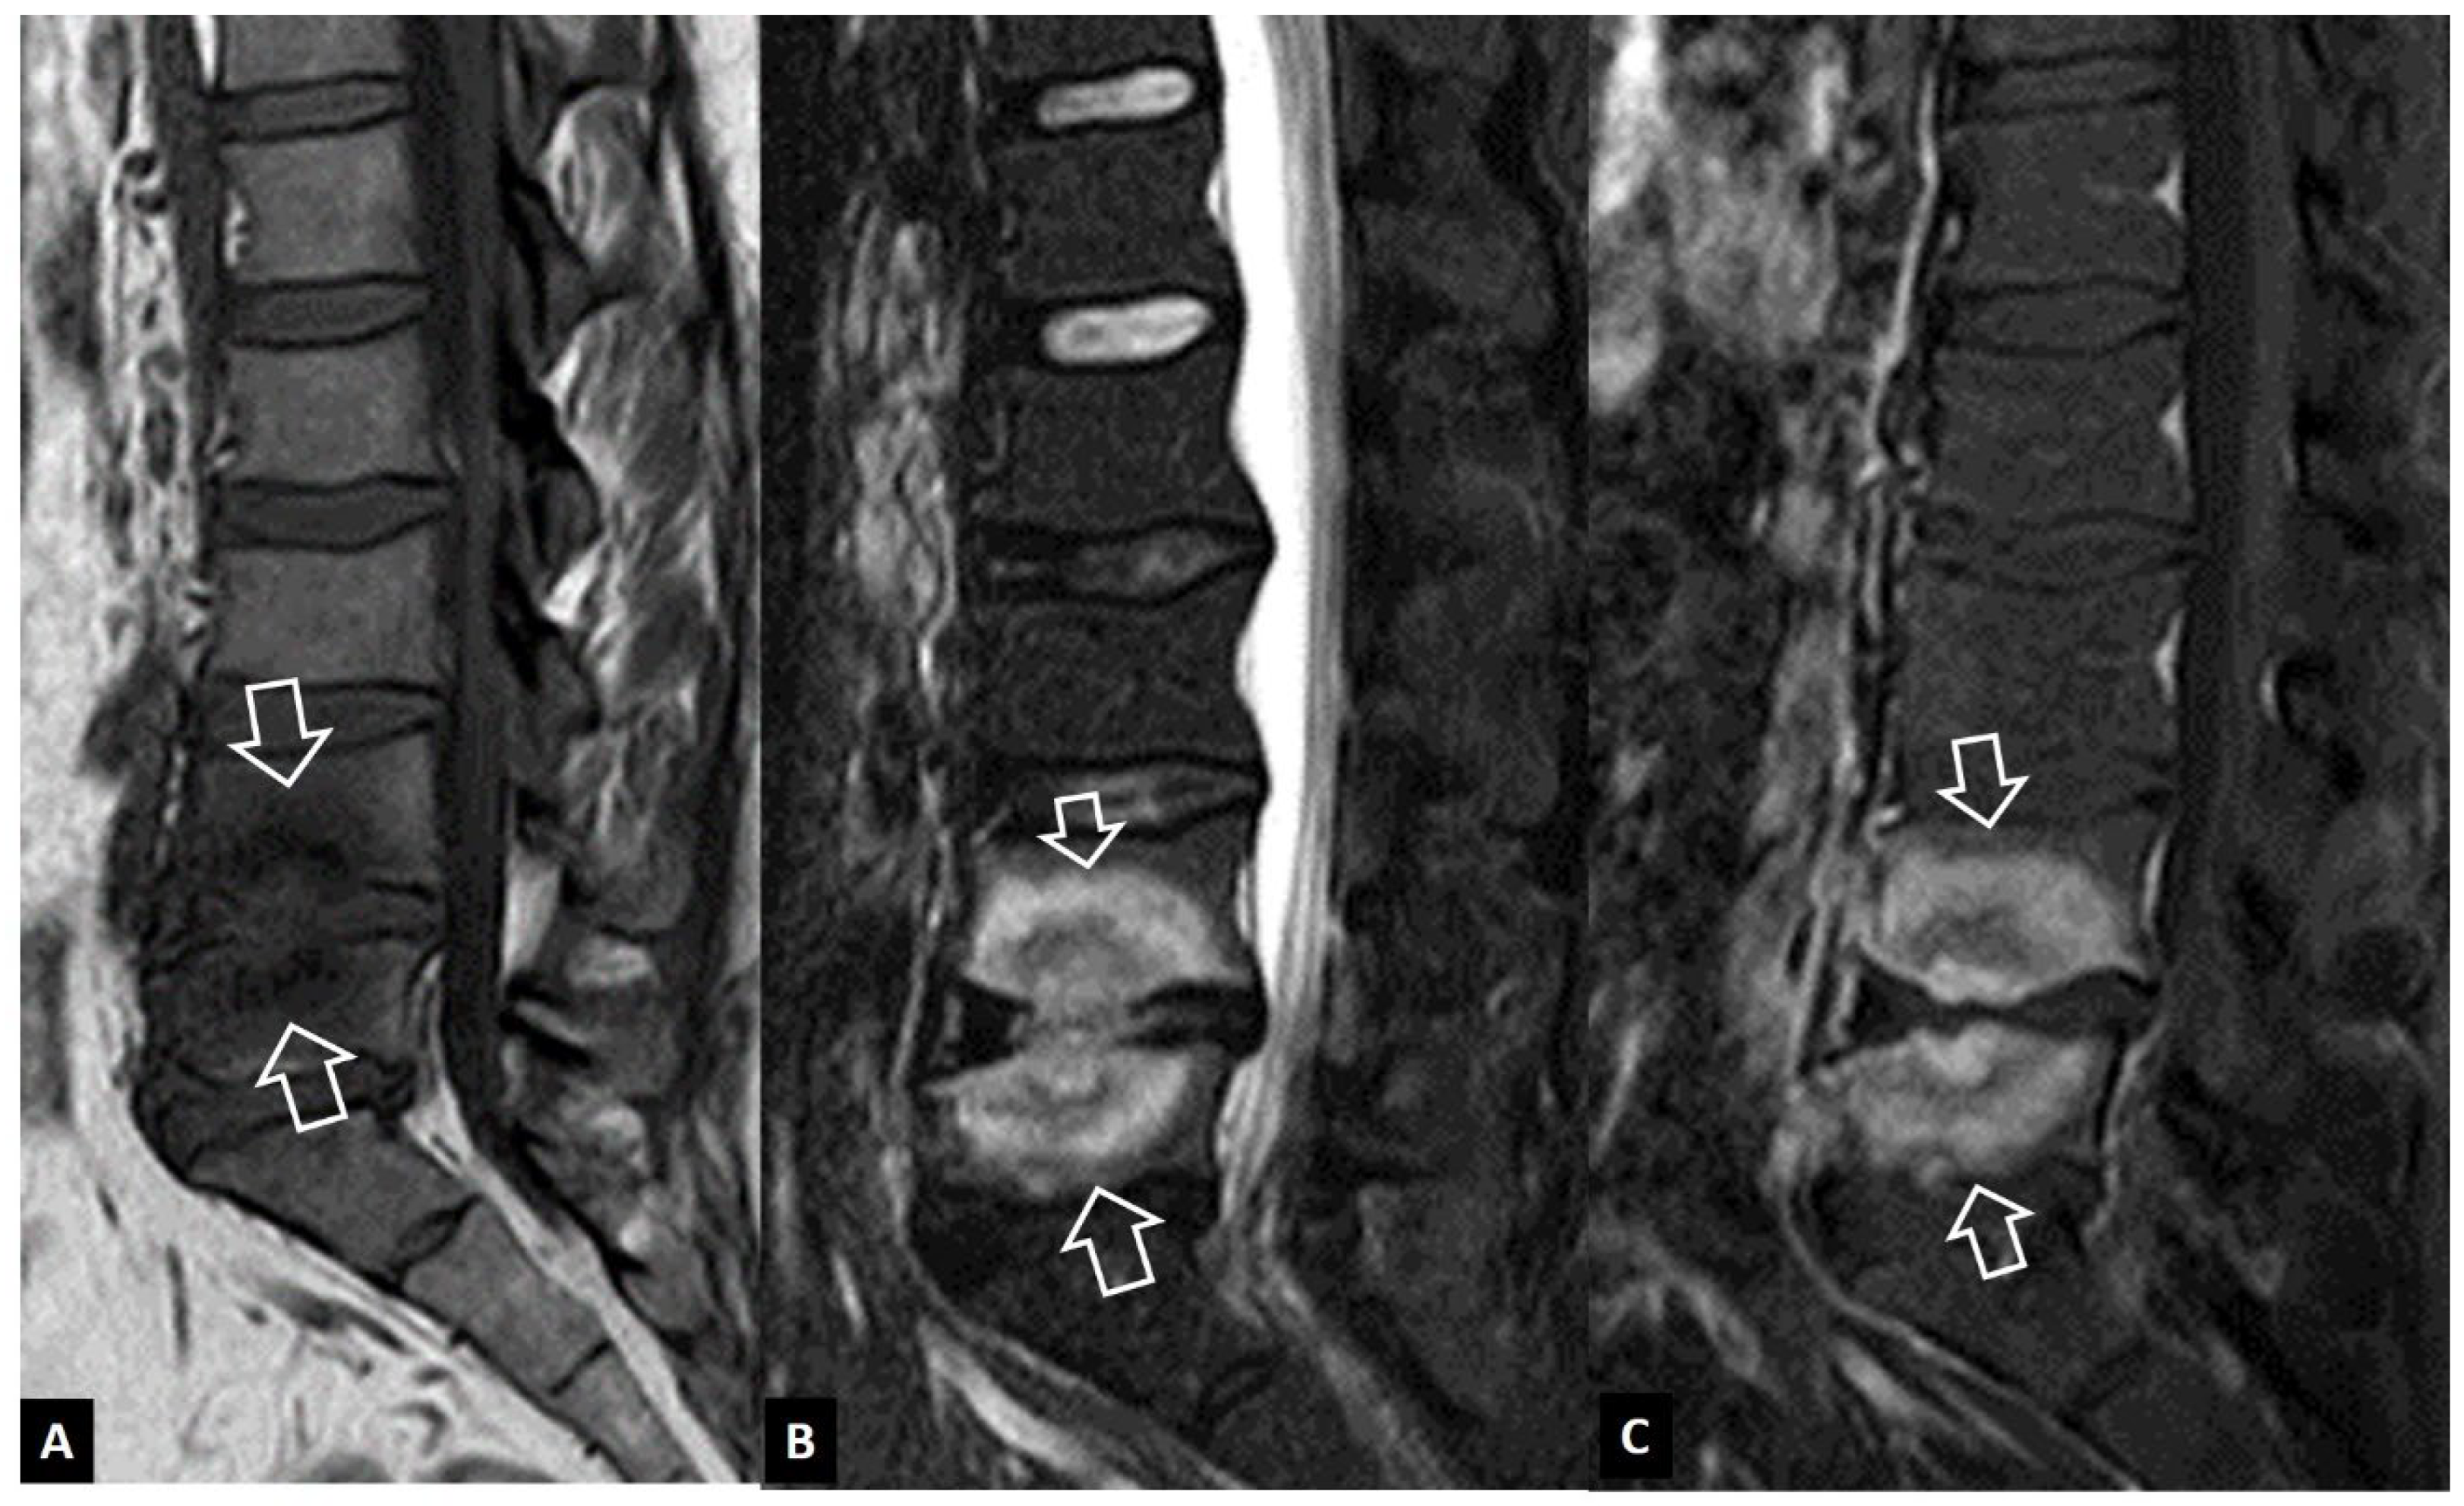

1. a.v. Crystal Deposition

1. a.vi. Postop Aseptic Discitis

1. a.vii. Trauma